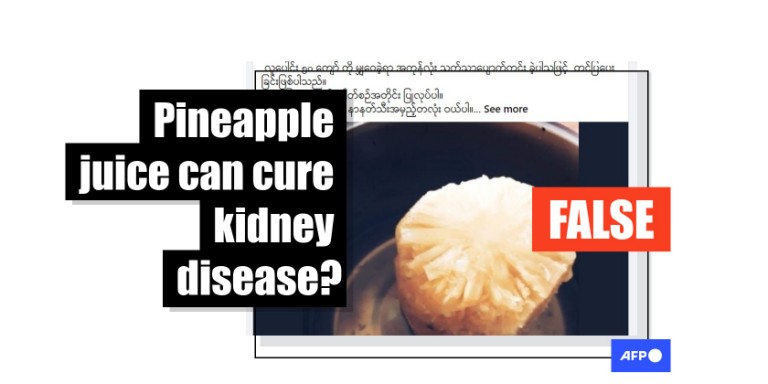

Pineapple and Kidney Stones: The Benefits

So, can pineapple help prevent kidney stones during pregnancy? While not a magic solution, pineapple does contain minerals and antioxidants that can help reduce the risk of kidney stones. The combination of water from pineapple and its high vitamin C content can help flush out excess oxalate, a common culprit behind kidney stone formation.